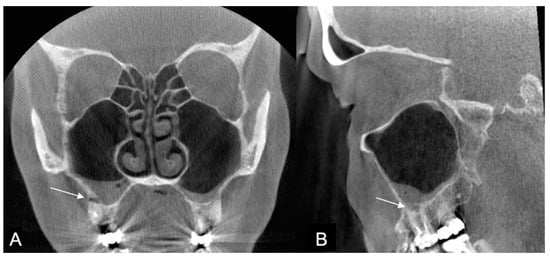

The origin of the artifacts in the CBCT images is given in Figure 5. The main origins of the artifacts were large dental fillings or crowns in the upper jaw, being present in 203/214 (95%) of the CBCT images (Figure 6). Endodontic fillings of the maxillary teeth were the reason for artifacts in 111/214 (52%) of the images (Figure 7), followed by fixed dental prostheses and dental implants (Figure 8) causing the artifacts in 28/214 (13%) and 5/214 (2.3%) of the CBCT images, respectively. Other implants in the maxillofacial area were found only in three CBCT images, resulting in artifacts in levels 2 and 3 (Figure 3).

Here, we also showed that endodontic fillings such as gutta-percha and root canal posts caused artifacts in 52% of the CBCT images (Figure 7). However, their role in causing detrimental artifacts and in diagnosing AP remains partly unknown. When assessing root-filled teeth, it is difficult to judge whether the artifact originates more from the crown material, the root filling, or the root canal post material. Regardless of the origin, root-filled teeth should be checked extra carefully, as AP is more common in root-filled teeth, and teeth restored with crowns [31,32,33,34]. Furthermore, periapical lesions are also more common in molar teeth and the mesiobuccal roots of maxillary first molars [31]. Maillet and coworkers reported that the maxillary first molar was the tooth associated most with a change in the maxillary sinus floor (55%), followed by the maxillary second molar (34%), the second premolar (8%), and the first premolar (3%). This order is most likely a consequence of the close location of the maxillary molar roots to the maxillary sinus floor and the earlier eruption of the maxillary first molar, causing a greater risk of carious lesions [35].

Due to artifacts, many authors still recommend intraoral images especially when dental implants are present, as seen in Figure 8 [40]. Therefore, a careful clinical judgment of the magnitude and materials used in dental restoration should be performed before referring patients for CBCT imaging.

Figure 7. The coronal slice of the CBCT image presenting root-filled teeth in the maxilla and some artifacts originating from the fillings.

Figure 8. The axial slice of the CBCT image presents multiple implants causing a substantial amount of artifacts.